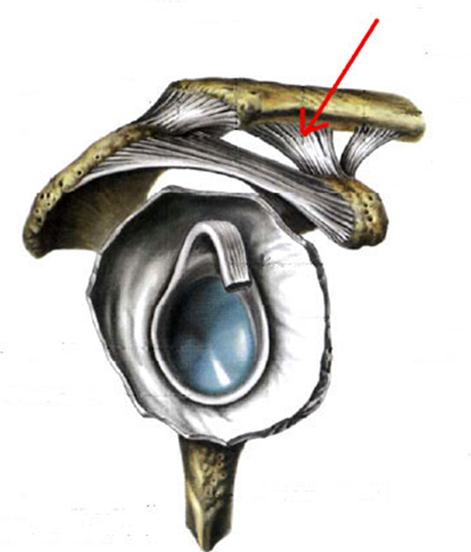

I:

S: Стрелка указывает на... плечевой кости.

-:tuberculum majus

+:tuberculum minus

-:epicondylus medialis

-:troсhlea

-:capitulum